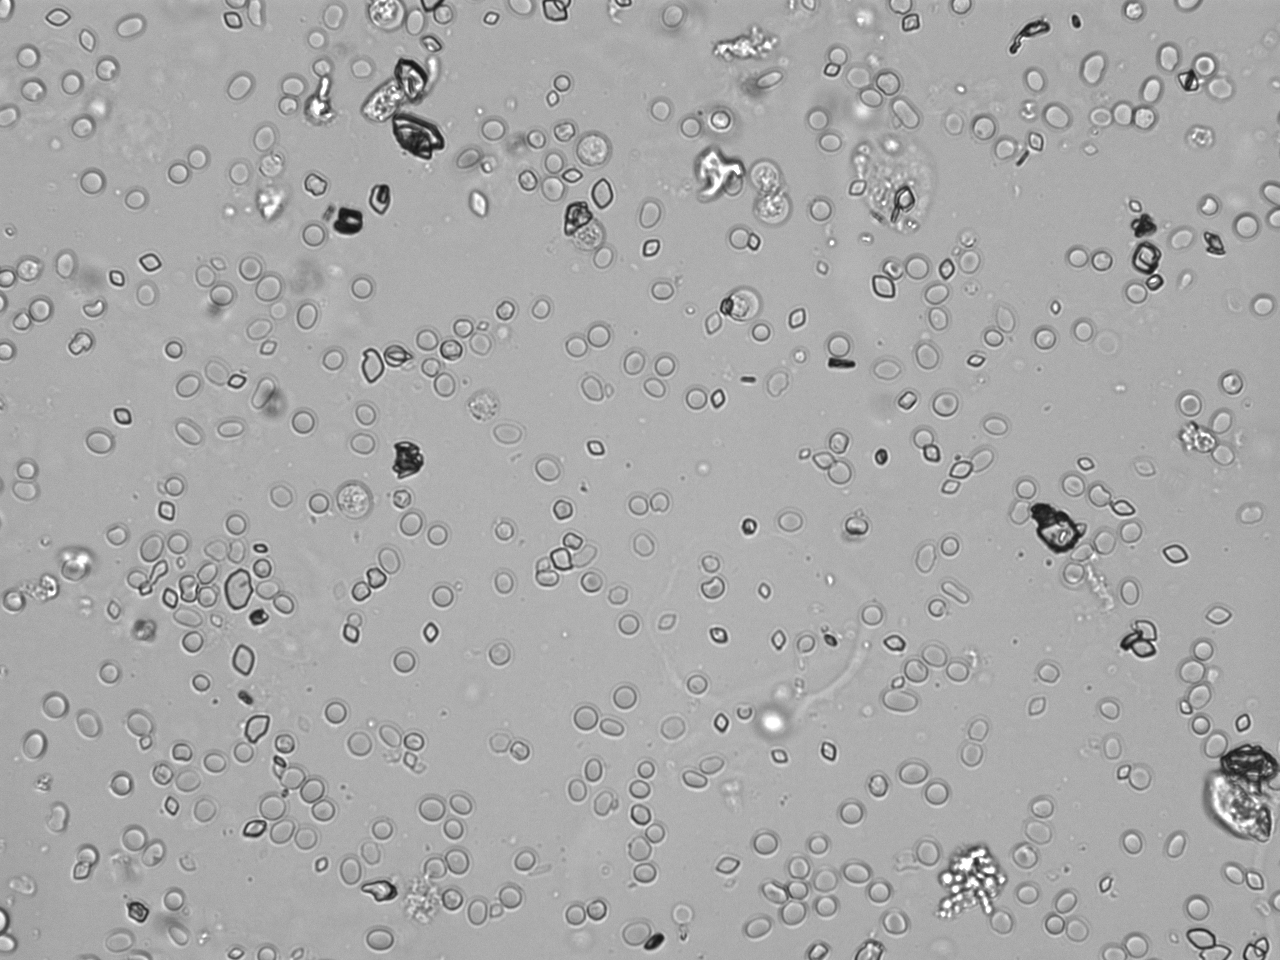

Urin-Feature: Harnskristalle_Rhomboid